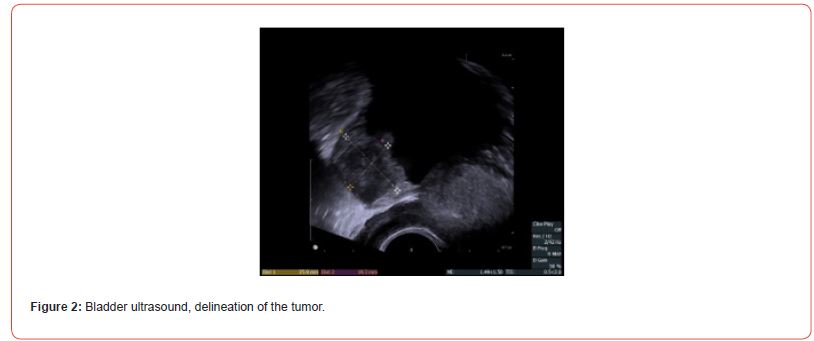

A 49-year-old patient presented with macroscopic hematuria. The CT scan revealed a protruding mass measuring 4 cm on the left postero-lateral wall of the bladder (Figures 1&2). Cystoscopy showed a fleshy polypoid mass near the left ureteral meatus. Bladder cancer was suspected, and an endoscopic resection was performed. Microscopic examination showed that the different samples involved the bladder wall, with a predominantly fusiform myofibroblastic cell proliferation arranged in a fascicular pattern and associated with inflammatory cells. At other locations, there were more star-shaped cells arranged in a myxoid stroma associated with inflammatory cells (mixed infiltrate characterized by neutrophils, eosinophils, plasma cells, lymphocytes). The myofibroblastic cells infiltrated the bladder wall diffusely. There was extensive invasion of the submucosa and invasion of the muscular layers. Some areas of tumor necrosis were present. The mitotic index ranged from 4 to 6 mitoses per 10 high-power fields. Many hemorrhagic changes were associated with this tumor proliferation. The tumor was invasive and poorly defined. Surface ulceration occurred.